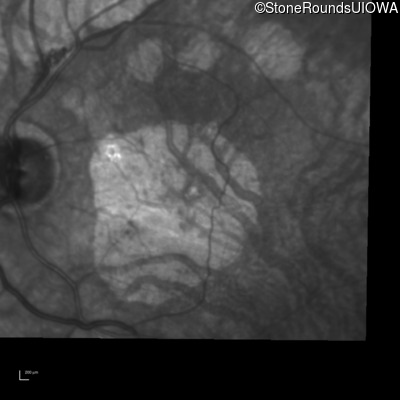

Infrared Fundus Photograph - Left - 20/100

Exemplar